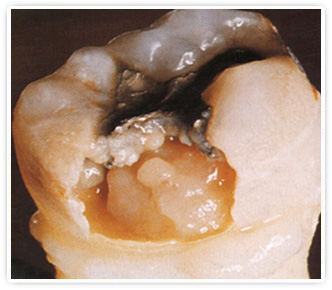

Лечение пульпита в ОрлеО развитии пульпита может свидетельствовать резкая зубная боль в ночное время в зубе, пораженном кариесом. Пульпит — это острое или хроническое воспаление пульпы, то есть мягкой ткани, состоящей из сосудов и нервов, заполняющей полость зуба. Чаще всего причиной пульпита бывает кариес, а также действие инфекции, проникающей в пульпу через корневые каналы или десневые карманы.

Основным симптомом пульпита является интенсивная зубная боль, возникающая преимущественное в ночное время или при перемене температуры. В начальной стадии заболевания боль может быть ноющей, возникающей периодически. При запущенном пульпите боль становится: